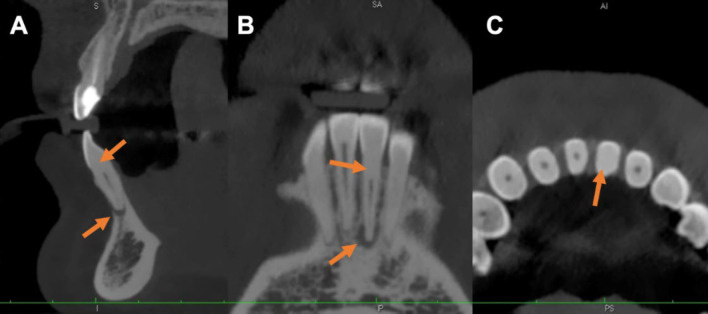

根管阻塞是由硬组织附着引起的,通常与有外伤史的牙齿、正畸运动、龋齿反应、靠近牙髓腔的修复手术以及老年患者的牙齿有关。根管治疗的术前规划应彻底,除辅助检查评估外,还包括对患者体征和症状的评估。一名 27 岁的患者患有下中切牙色素沉着症,有牙科外伤史,对垂直叩击有阳性反应,初次根尖周炎 X 光片显示根管钙化和根尖周炎病变。患者表现为咀嚼时疼痛,触诊和垂直叩诊试验均呈阳性反应。诊断结果为无症状根尖牙周炎。患者要求进行锥形束计算机断层扫描,并进行了表面扫描以建立静态导向。通过微创方法从牙根的中间三分之一处进入根管,并找到了根管位置。根管治疗采用传统方法。结果显示,经过 3 年的临床和放射学随访,治疗取得了成功。因此,在钙化根管病例中使用根管治疗引导器可以大大减少临床医生的工作时间,并为这些病变的治疗提供了一种更可预测的方法。

Root canal obliteration is caused by hard tissue apposition and is often associated with teeth with a history of trauma, orthodontic movement, caries reaction, restorative procedures near the pulp chamber, and teeth of elderly patients. Preoperative planning of root canal treatment should be thorough and include an assessment of the patient's signs and symptoms in addition to the evaluation of complementary examinations. In a 27-year-old patient with dyschromia of the lower central incisor, a history of dental trauma, and a positive response to vertical percussion, an initial periapical radiograph was obtained that showed calcification of the canal and presence of a periapical lesion. The patient presented with pain on chewing, a positive response to palpation and a vertical percussion test. The diagnosis was symptomatic apical periodontitis. A cone-beam computed tomography scan was requested and a surface scan was performed to establish a static guide. The root canal was accessed in the middle third of the root and the canal was located using a minimally invasive approach. The root canal was treated conventionally. Results obtained showed the success of the treatment after a 3-year clinical and radiographic follow-up. Therefore, the use of an endodontic guide in cases of calcified canals significantly reduces the clinician's working time and offers a more predictable approach to the treatment of these pathologies.